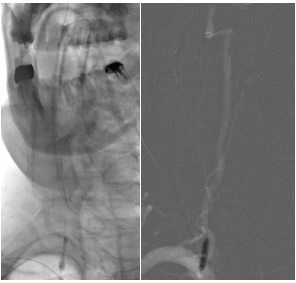

▲右侧颈内动脉颅外段重度狭窄,左侧颈内动脉代偿右侧颅内

考虑患者此次少量蛛网膜下腔出血与颅内动脉瘤无关。患者右侧颈内动脉重度狭窄,左侧椎动脉颅内段闭塞,后循环供血完全依赖于右侧椎动脉,因此右侧椎动脉起始重度狭窄合并远端动脉瘤手术指征明确。结合患者“狭窄+动脉瘤”同时存在的现状,经过医院神经外科讨论,脑血管病介入组提出了治疗方案,即:一期(一次手术)行“椎动脉狭窄支架植入+动脉瘤支架辅助弹簧圈栓塞术”。手术的关键在于策略和顺序:既要恢复血流,又要防止斑块脱落,还要确保动脉瘤致密栓塞。

第一步,通路建立与保护。经股动脉穿刺建立通路。考虑到狭窄程度重,导引导管难以通过椎动脉开口,强行通过易导致斑块脱落,甚至损伤血管内膜致夹层。刘磊副主任医师应用小球囊穿梭技术顺利引导导引导管通过椎动脉起始狭窄处,到达指定位置。

第三步,解除狭窄,恢复血流。选择合适尺寸的球囊扩张式支架,精准释放于右侧椎动脉起始部狭窄段。